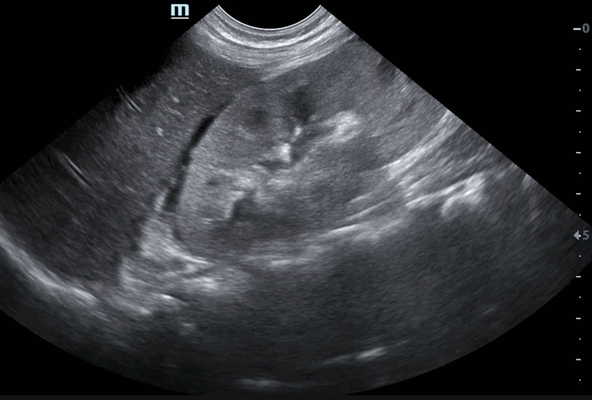

Под диафрагмой справа визуализировалось гиперэхогенное опухолевидное образование несколько неоднородной солидной структуры, с четкими ровными контурами, размером 50x38x35 мм. К нижнему полюсу данного образования прилежала правая почка, имеющая нормальные размеры, форму и структуру. Нижняя полая вена была смещена кпереди и влево. Обращала на себя внимание выраженная гепатомегалия, причем структура печени не была однородной. Она содержала множественные гиперэхогенные включения размерами до 17 мм, окруженные тонким гипоэхогенным периферическим ободком. Цветовое допплеровское картирование(ЦДК) демонстрировало интенсивную периферическую васкуляризацию опухоли (рис. 1-3).

Рис. 1. Нейробластома правого надпочечника плода. Беременность 31 нед 4 дня.